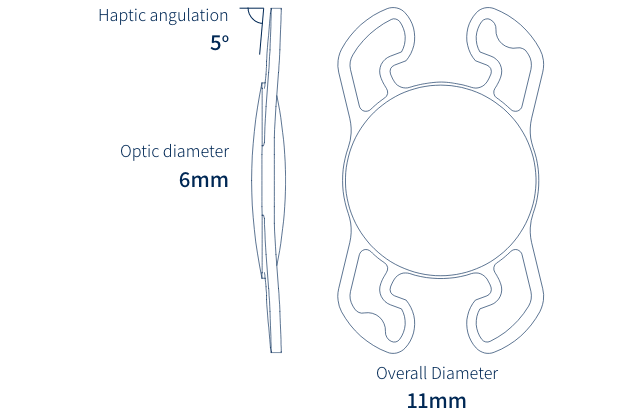

BunnyLens

BunnyLens